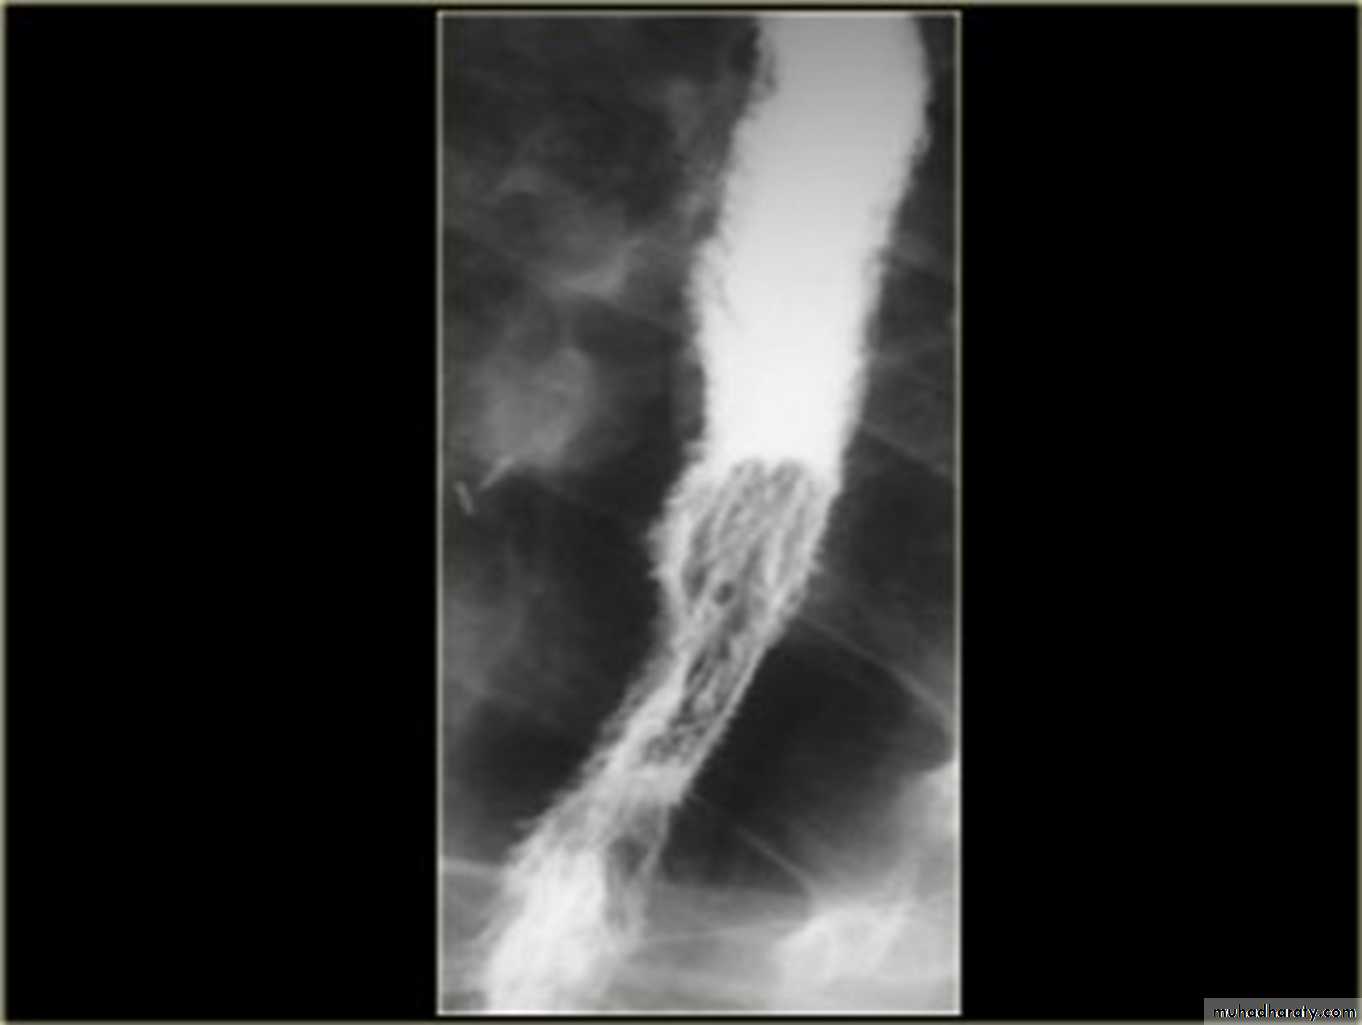

Candida esophagitis:in patient with an infectious esophagitis due to candida , the barium shows numerous fine erosions & plaques causing shaggy outline of the osophagus due to Candida albicans in immunocompromised patient.

middle year old female with a past medical history significant for HIV/AIDS comes in with complaint of loosing their weight over the past 2 weeks with pain & difficulty on swallowing …. Also feels like food is getting stuck in her throat

What is your diagnosis ??????????